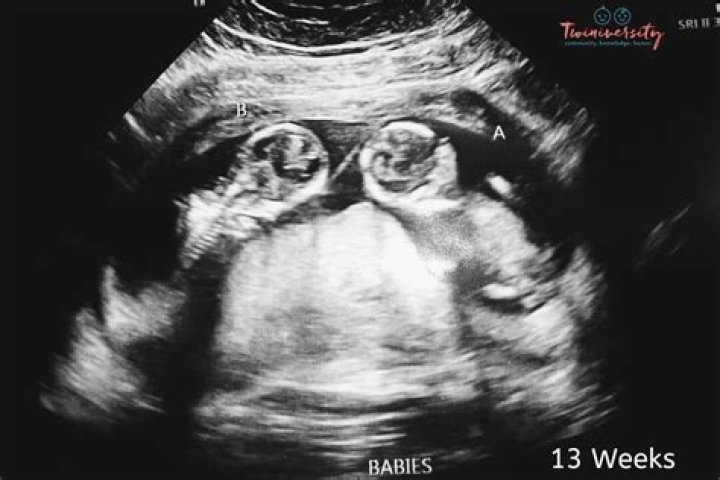

Doctors are able to diagnose most cases of achondroplasia even before birth by doing an ultrasound in the later stages of pregnancy. The ultrasound can show if a baby’s arms and legs are shorter than average and if the baby’s head is larger.

Imaging. Doctors may spot signs of achondroplasia, such as shorter limbs, or other causes of dwarfism on ultrasounds of a fetus during pregnancy. X-rays of babies or children may show that their arms or legs are not growing at a normal rate, or that their skeleton shows signs of dysplasia.

What are signs of dwarfism in ultrasound?

• a larger head with a prominent forehead.

• a flattened bridge of the nose.

• shortened hands and fingers.

• a sway of the lower back.

• bowed legs.

When does achondroplasia appear in ultrasound?

Discussion. Nowadays, achondroplasia is suspected only after the third trimester due to the late appearance of this disease [2]. These fetuses almost always have a long bone below the third percentile for gestational age but normal size of head and abdominal circumference [2], [8], [9], [10].

Achondroplasia is generally detected by abnormal prenatal ultrasound findings in the third trimester of pregnancy. It is then confirmed by molecular genetic testing of fetal genomic DNA obtained by percutaneous umbilical blood sampling (PUBS).

Achondroplasia can be diagnosed before birth by fetal ultrasound. This test uses sound waves and a computer to create images of the baby growing in the womb. DNA testing can also be done before birth to confirm fetal ultrasound results. The condition can also be diagnosed after birth with a physical exam.